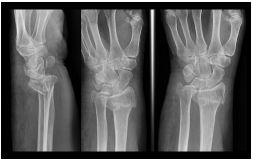

57 一位 65 歲婦人,主訴於 2 天前走路跌倒,右腕疼痛腫脹就診,如 X 光片顯示,下列敘述何者錯誤?

(A)復位後夾板固定,掌側夾板和尺側夾板的下端應超過腕關節,而背側夾板和橈側夾板則不超過腕關節 (B)此為伸直型橈骨下端骨折 (C)正常人橈腕關節面向掌側傾斜約 10~15 度,向尺側傾斜約 20~25 度 (D)外觀為「餐叉樣」(silver fork)畸形